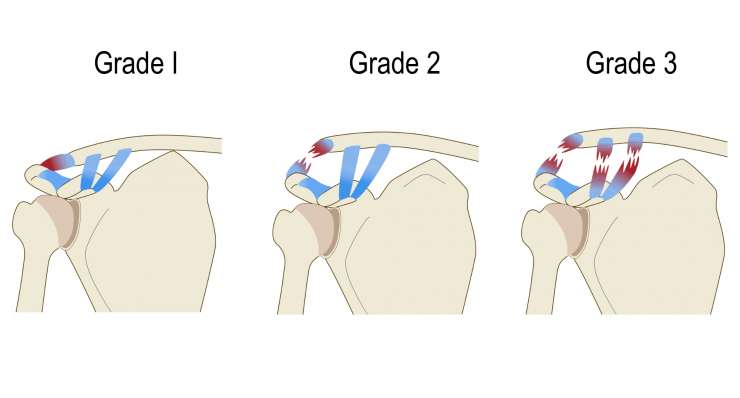

повреждение вращательной манжеты

Повреждение вращательной манжеты приводит к боли и потере функциональности плеча. В зависимости от результатов обследования, профессор, доктор медицины Франк Мартешлегер лечит это заболевание консервативным методом или с помощью артроскопии, проводя точную реконструкцию сухожилий.